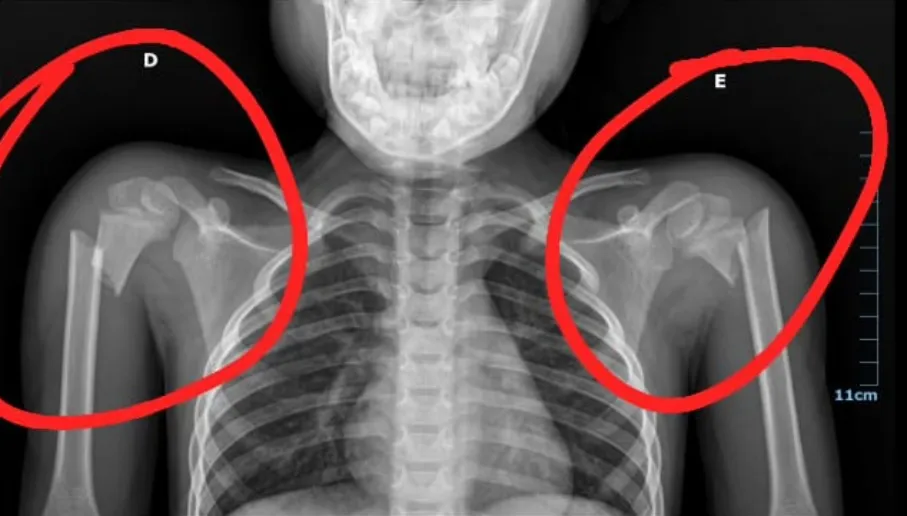

O menor estava na cadeirinha acompanhado do pai, no carro que seguia sentido à Santa Quitéria. Ele recebeu os primeiros atendimentos no Hospital Geral de Catunda e, posteriormente, foi transferido para o Hospital Municipal Zezé Benevides, onde foram identificadas as fraturas nos dois braços, na altura dos ombros.

Nos dias seguintes, porém, ele continuou sentindo dores intensas. Nesta segunda-feira (17), 11 dias após o fato, a família procurou novamente o Hospital Municipal de Santa Quitéria. Uma nova radiografia foi feita e surpreendeu a todos, ao mostrar que as fraturas permaneciam na mesma condição do dia do acidente, indicando que o procedimento informado anteriormente não foi realizado.